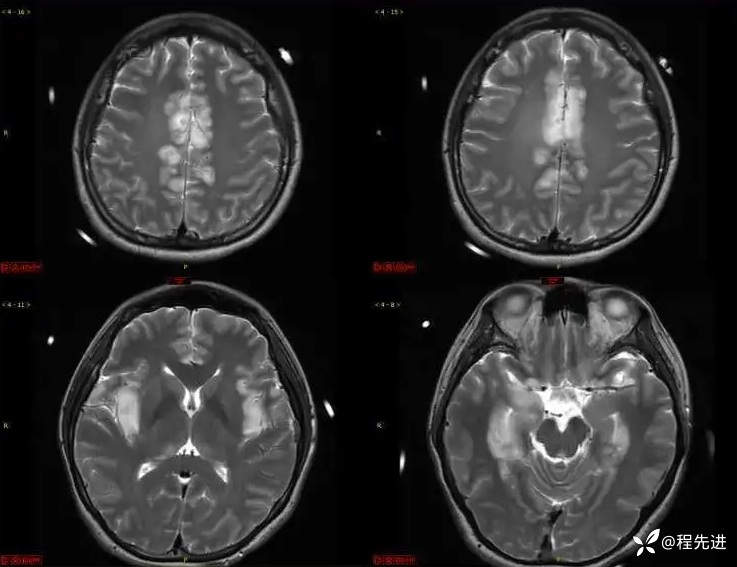

T2: